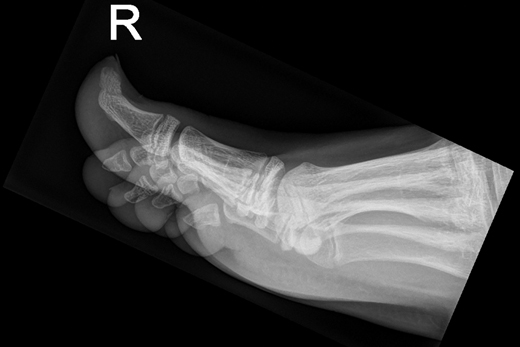

Patiënte B, een 49-jarige vrouw, bezoekt de huisarts met een pijnlijke granulomateuze zwelling, subunguaal aan de mediale zijde van de linker hallux [figuur 3]. Histologisch onderzoek door de huisarts vermeldt acanthose en hyperkeratose, zonder duiding van maligniteit. Het röntgenonderzoek toont het beeld van een subunguale exostose en de patiënte krijgt een verwijzing naar de orthopedisch chirurg voor excisie [figuur 4].

De voet van patiënte B.